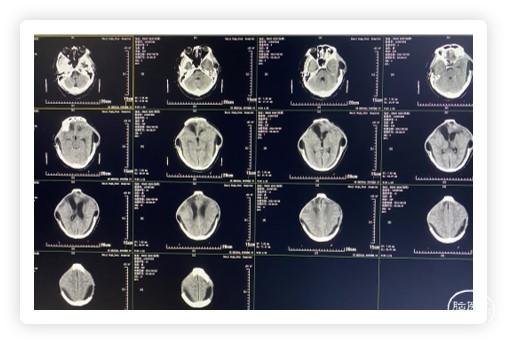

5月26日CT(术后第7天)

CT提示:环池、三脑室、双侧侧脑室显露良好

6月7日复查CT(术后第18天)

患者反应较前明显迟钝,强刺痛可睁眼,CT检查提示:环池、三脑室消失,双侧侧脑室变小,双侧颞顶枕硬膜下积液,额叶血肿吸收期。

6月8日复查CT(术后第19天)

患者反应较前明显好转,CT提示:环池、三脑室显露,侧脑室较前恢复。

6月29日复查CT(术后第30天)

CT检查提示:脑室系统较前明显扩大,并双侧脑室前角间质性水肿,硬膜下积液较前稍有吸收。